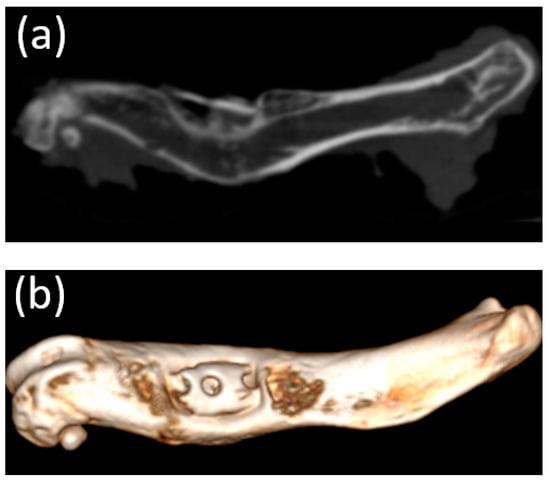

3.5. Micro-CT